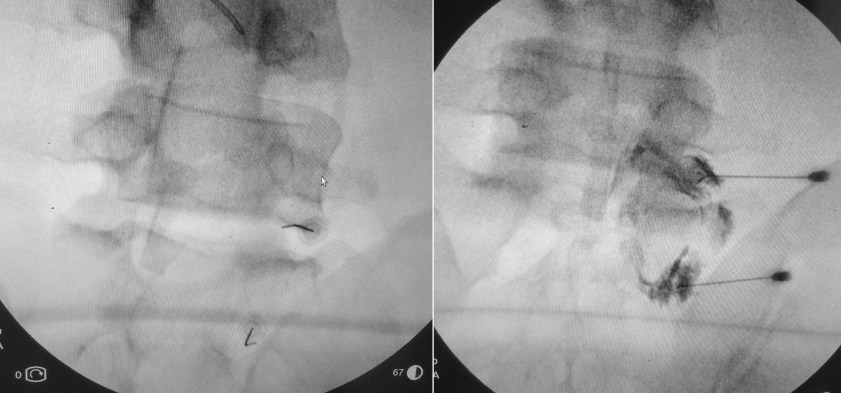

Resim 2: Sağ L5-S1 forameni ve S1 foramenleri yoluyla epidural enjeksiyon uygulanması.

Enjeksiyon ameliyathanede, hasta yüzüstü pozisyonda karın altı desteklenerek, skopi altında ve kontrast madde kontrolü ile (300 mg/ml Ultravist), 20G kalınlığında ve 9 cm uzunlugunda spinal iğneler kullanılarak steril teknikle uygulandı. Toplam 20-30 ml hacminde olmak üzere %1 adrenalinsiz Lidokain + serum fizyolojik + ½ ampul depo steroid verildi. L5-S1 seviyesinde infranöral teknik kullanılmıştır. Sağdaki resimde her iki foramenden de epidural alana uygun kontrast geçişi görülmekte. Daha iyi ağrı kontrolü amacıyla aynı seansta sağda L2-S1 medial dal blokları da yapıldı.